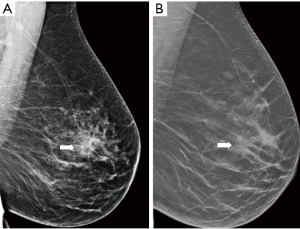

Figure 11 Mammography of the right breast in medio-lateral-oblique (A) and cranio-caudal view (B) with multiple densities with irregular margins and architectural distortions (arrows). Ultrasound (C) shows more than two hypoechoic lesions of suspicious features. In MRI (D) an extensive area of tumour involvement is revealed. MRI, magnetic resonance imaging. - A patient of 50 years of age evaluated for enlarged lymph nodes in the axilla. Mammography and ultrasound show enlarged pathological lymph nodes in the axilla, otherwise no pathological finding in the breast on initial evaluation despite the low mammographic density. The largest lymph node is biopsied proving metastatic invasive carcinoma NST of breast origin. MRI is indicated to search for an occult lesion in the breast. MRI shows the enlarged lymph nodes and a small lesion in the right breast in upper outer quadrant. A second-look, targeted ultrasound with the knowledge of the location of the lesion is performed to reveal a small suspicious lesion, which is subsequently verified as the primary tumour in the breast (Figure 12).

Figure 12 Enlarged lymph node in the right axilla is seen in mammography (A). In MRI (B) enlarged lymph nodes (star) are confirmed and a small mass with early intense enhancement in the upper outer quadrant (arrow). In ultrasound (C) the lesion is very subtle (arrow). MRI, magnetic resonance imaging. - Preoperative marking. Microcalcification with ductal distribution biopsied by vacuum—assisted biopsy under mammography guidance as DCIS grade 2; the extent of the calcifications is approximately 30 mm. Marking by two wires is performed to delineate the extent of the disease. A specimen mammography of the resected tissue shows both wires with microcalcifications between them that do not reach the margins (Figure 13).